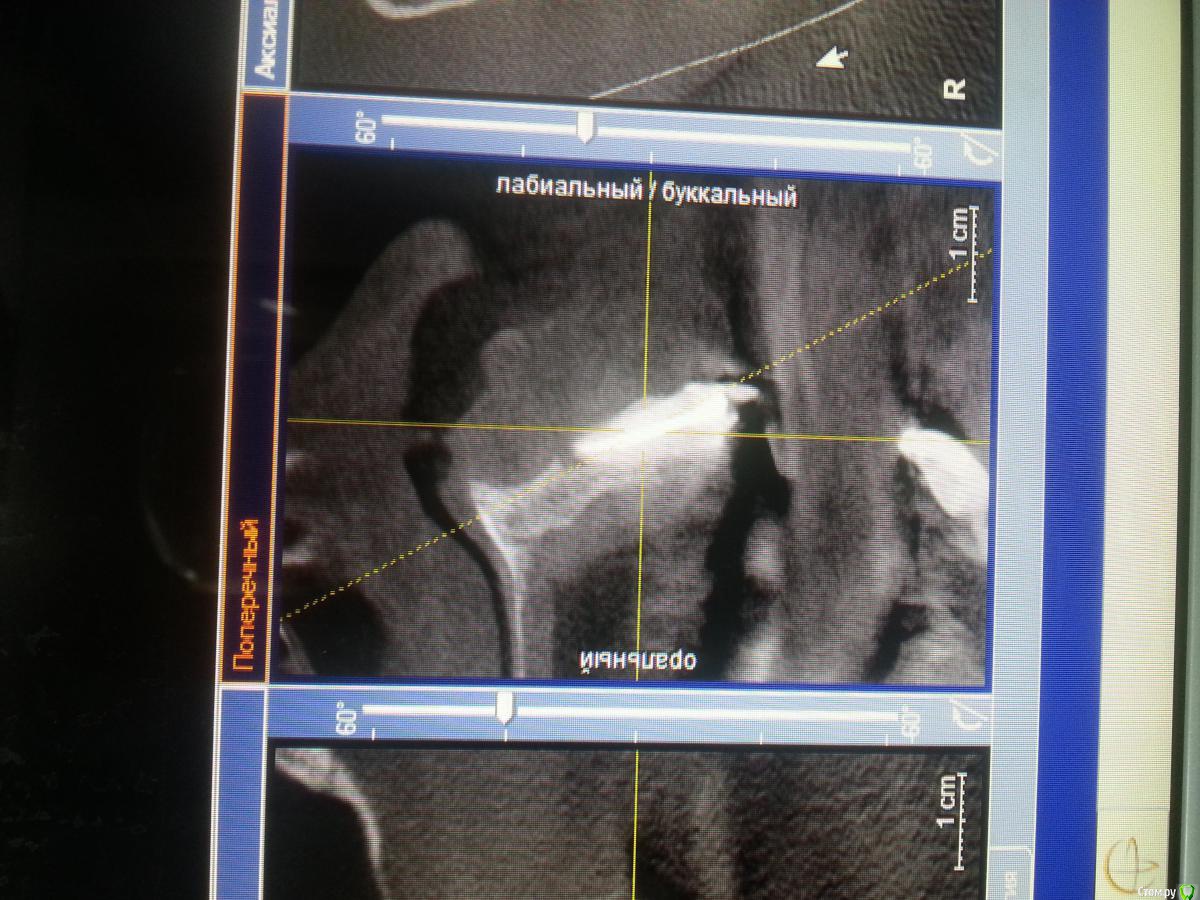

nata2016 Опубликовано 28 сентября, 2016 Поделиться Опубликовано 28 сентября, 2016 Планируется удаление 1.3 и имплантация. Потом гибридный мост 2.1 и2.2. Как думаете лучше их тоже удалить? Пациентка говорит была резекция и это видно на кт.так же виден очаг в области 2.1.проблема в нехватке денег у пациентки. Посоветуйте как бы поступили вы. Ссылка на комментарий